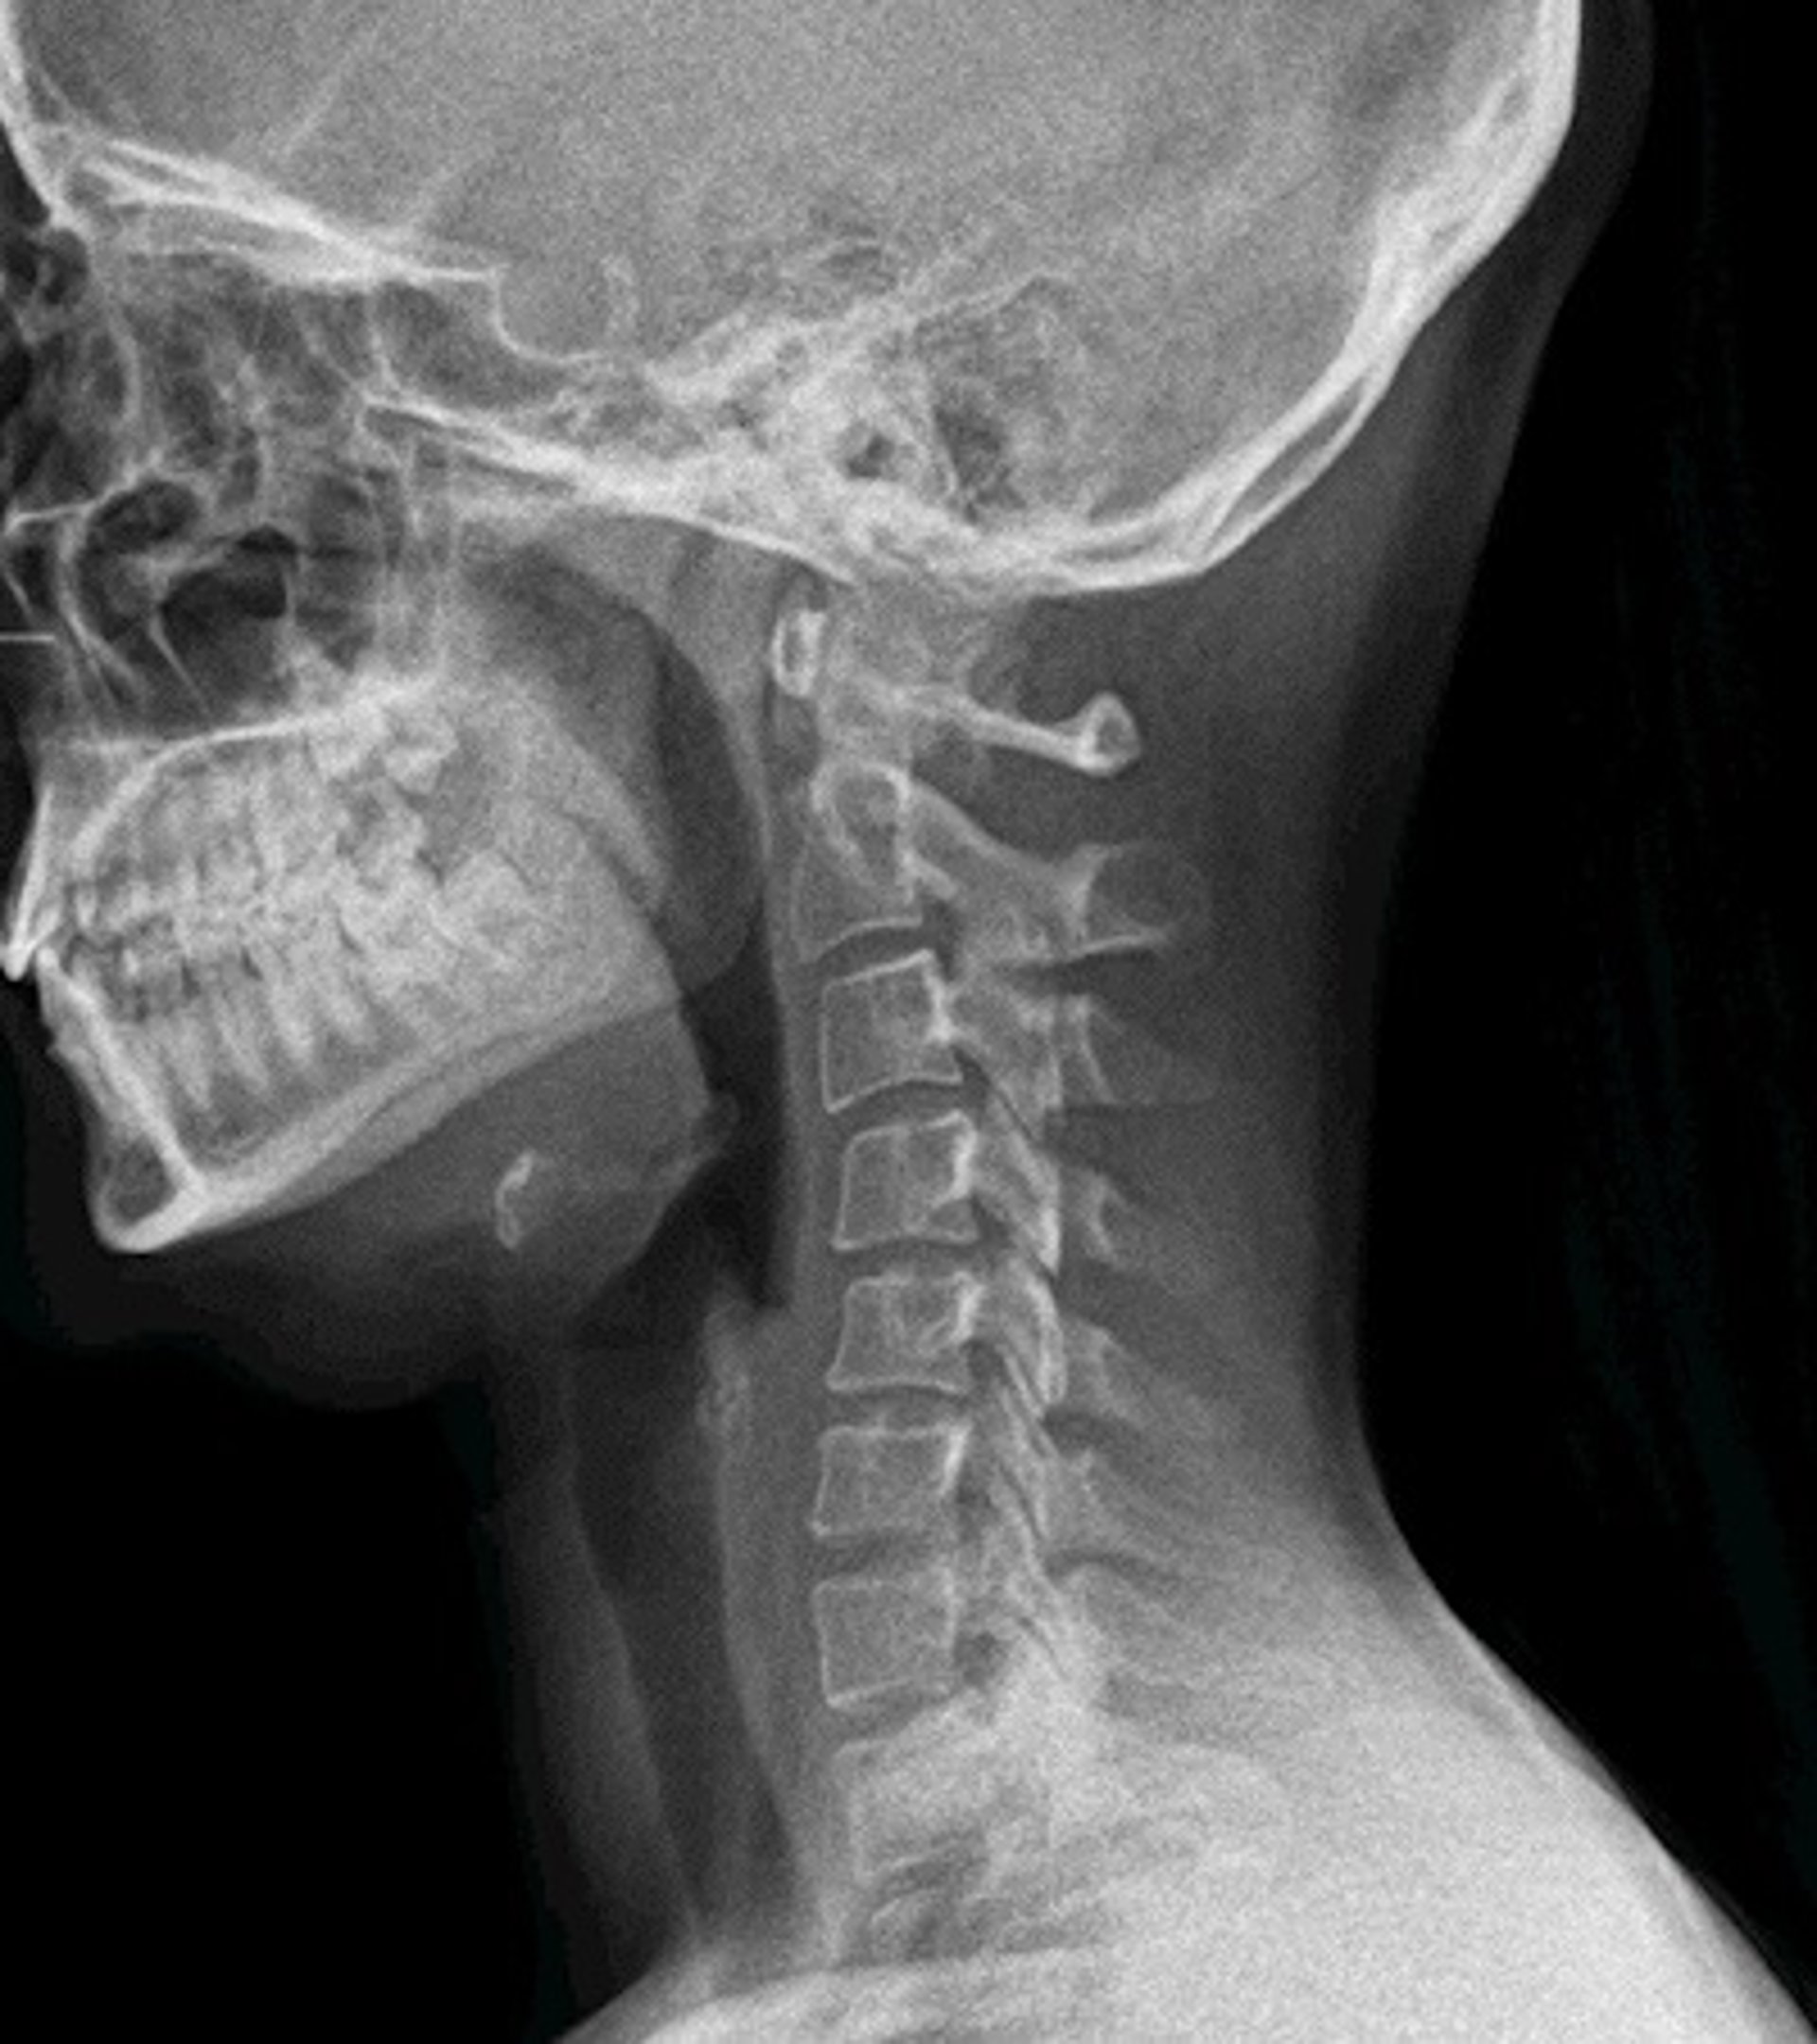

Según señalan, en la actualidad sólo existen estos equipos en Japón y Estados Unidos. La radiología digital dinámica (Dynamic Digital Radiography -DDR, por sus siglas en inglés) es una innovadora tecnología de rayos X que permite obtener series de imágenes digitales en la que se aprecia la anatomía en movimiento.

"El equipo, emite 15 pulsos por segundo durante un tiempo de exposición de 15 segundos, lo que ofrece una imagen dinámica de la anatomía del paciente de forma muy rápida", explica el doctor Vicente Martínez de Vega, jefe del Servicio de Diagnóstico por la Imagen del Hospital Universitario Quirónsalud Madrid, que dispone del primer equipo portátil en Europa de estas características.

Este equipamiento de la empresa Konica Minolta ofrece a los radiólogos la posibilidad de capturar y analizar el movimiento fisiológico de una estructura corporal con una dosis muy inferior a un estudio por fluoroscopia. "La radiología digital dinámica tiene utilidad en los estudios ortopédicos en los que se aprecia una imagen radiográfica del movimiento de las articulaciones como la muñeca, el hombro o la rodilla. También tiene gran utilidad para estudiar la columna en flexión y extensión", explica.